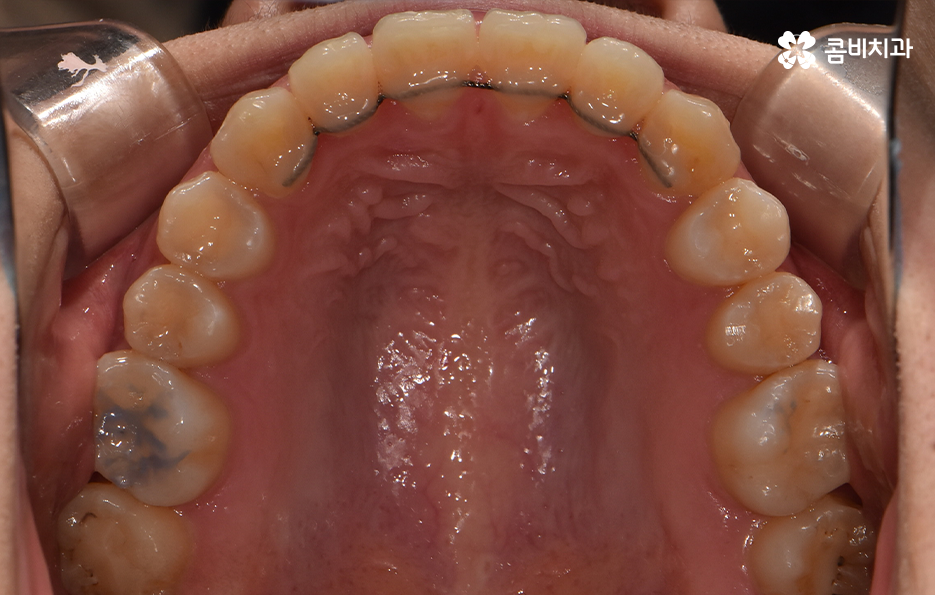

덧니는 윗니와 아랫니에 모두 있거나 앞니에 살짝 있는 수준의 덧니도 있으며 덧니가 심한 경우에는 개방교합으로 인해 입이 잘 다물어지지 않는 경우도 있기 때문에 덧니가 심한 정도에 따라서 치아교정의 계획은 세부적으로 달라질 수 있어요

덧니가 심하지 않은 경우에는 비발치로도 충분히 교정을 하는 경우도 있겠지만 덧니가 심한 경우에는 덧니 발치 교정을 통해서 치료가 진행되는 경우가 많이 있는데요. 그 이유는 치아교정의 원리를 생각하더라도 치아를 재배치하기 위해서는 기존의 치아가 움직일 공간이 필요한데 덧니는 치열이 이미 완성되고 있는 상태에서 치아가 나올 공간이 부족하여 덧니가 되는 경우가 많다는 점에서도 치아의 이동 공간을 확보하기 위한 발치가 필요할 수 있는 거예요

교정을 위해 치과에 가보시면 3D CT 등을 활용하여 3차원 정밀 분석을 통한 치료 후 시뮬레이션 결과까지 직접 보면서 확인할 수 있는데요. 발치 교정을 하면 비발치 교정에 비해서 얼굴 변화가 보다 크기 때문에 치료 후 결과에 대한 예측은 매우 중요한 과정으로 볼 수 있어요